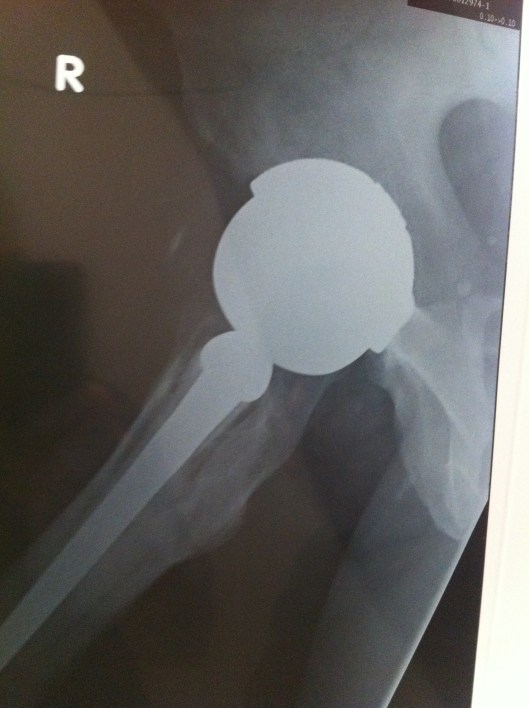

X-rays were taken in the Gold Coast Hospital Outpatients Clinic while I waited – great service – thanks guys!

The x-rays confirmed the arthritis in the left hip and this is going to need replacing.

However, it was the right hip, with the Smith & Nephew Birmingham Spectron total hip replacement which caused the most interest:

- Severe oestolysis around the hip – tissue damage.

- Bone erosion (gone totally) for several centimeters below the collar on the inside leg side.

- Damage to the bone on the outside leg side – mottled and insubstantial-looking.

- Signs of movement of the femoral stem of the hip implant – lines down either side and possible bone damage – the cement contains ceramic and this can then act as a grinding past as the stem moves. This has the potential to release more metal ions.

- These signs of movement may explain the feeling of “popping in and out” that I feel – but without dislocation of the hip prosthesis.

We reviewed my X-rays and confirmed the osteolysis and bone loss. The health of the bone at the top of the femur is a concern and I am going to have a nuclear medicine bone scan tomorrow morning to see what is going on with the blood flow to and around the bone.

The movement of the prosthesis, or lines suggesting movement within the femur where obvious (it seems?).

Had some new X-rays done today – two months since the last ones – seems to me that there is more osteolysis and bone loss – possibly some fragments but I am not a medical doc and I haven’t discussed these with the surgeon yet. Will do on the day of the surgery.

What is interesting is 3 radio-opaque spots showing up in the pelvic area – not sure what those are.

Quality of the photo’s below – OK for an iPhone 4 shot of the X-Rays held up by my son against a white background!